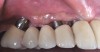

Following a similar paradigm of treating peri-implantitis the same way that periodontitis is regularly successfully treated, based on the mechanical removal of biofilms adhered to implant/abutment surfaces, different protocols of nonsurgical implant debridement using different mechanical, physical, and chemical mechanisms have been evaluated (Figure 12 through Figure 15). In general, the use of different protocols combining treatments aimed to decontaminate the implant surface (eg, mechanical, lasers) and control the infection process (eg, antiseptics, antibiotics) have shown clinical and significant improvements in the commonly used surrogate outcomes (mean reductions in PPD of around 1.2 mm and mean reductions in the scores of BOP of about 50%) but have not resulted in disease resolution18 or a high degree of predictablility.19 There is currently no specific nonsurgical therapy that has shown efficacy in the resolution of peri-implantitis, and the clinical improvements reported in the clinical studies were not sufficient for the arrest of the disease, leaving the standard of care in the treatment of peri-implantitis as surgical in most cases.20

Fig 12. Treatment of peri-implantitis: peri-implant mucosal inflammation associated with plaque and calculus accumulation.

Figure 12

Fig 13. Radiograph depicting crestal bone loss around mandibular implants.

Figure 13

Fig 14. After removing the prosthesis, presence of peri-implant plaque and calculus.

Figure 14

Fig 15. Access flaps to allow mechanical debridement of implant surfaces.

Figure 15